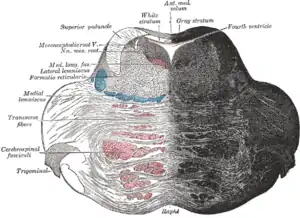

Location and topography of pons (animation) Axial section of the pons, at its upper part

Axial section of the pons, at its upper part Hind- and mid-brains; posterolateral view